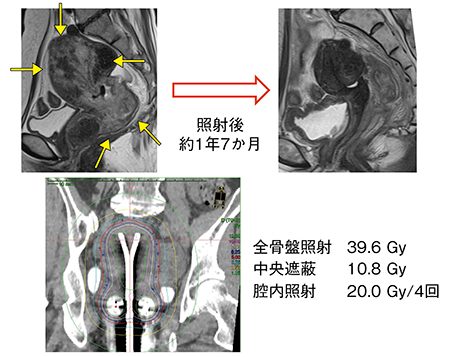

症例2は,Ⅱb期の子宮頸がん(腺扁平上皮癌)で体部浸潤を伴う。タンデム1本では照射が不十分なため,子宮体がん用のアプリケータと子宮頸がん用のオボイドを用いて,さまざまにミックスした治療を行った(図4)。照射後1年7か月が経過しているが,局所制御されている。

図4 症例2:体部浸潤を伴うⅡb期の子宮頸がん(腺扁平上皮癌)